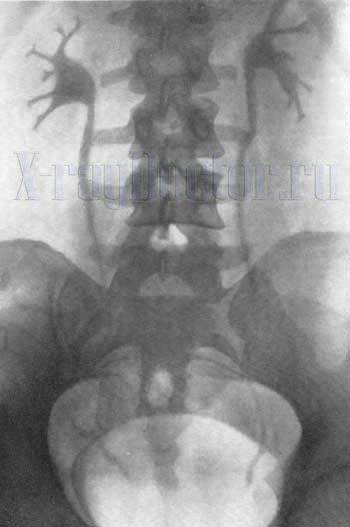

Экскреторная урография с использованием урографина и насыщением мочевого пузыря кислородом позволяет четко визуализировать лоханки и чашечки, а также мочевой пузырь с ясными и ровными контурами.

На 7-й минуте контрастное вещество начинает поступать в лоханку. На 15-й минуте наблюдается полное наполнение лоханок и уретры, что позволяет оценить состояние чашечек лоханок, а также положение и ход мочеиспускательного канала. На этом этапе получается четкий контрастный снимок, который легко интерпретировать рентгенологу. На изображении видны не только анатомические структуры, но и движение урографина.

На 21-й минуте рентгенограмма почек демонстрирует состояние мочевого пузыря.

Экскреторная урография: незначительное снижение тонуса мочевыводящих путей